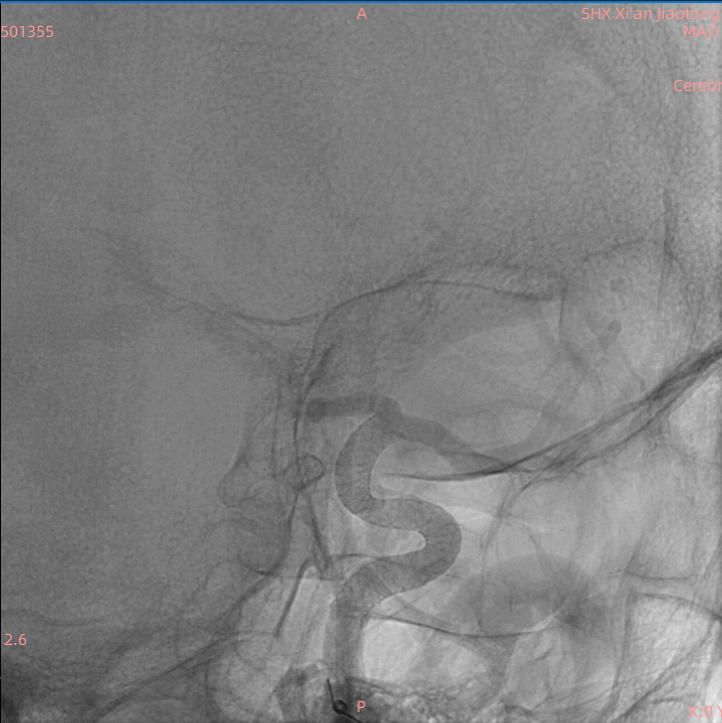

术后侧位造影见支架打开满意各分支血管通畅

术中全身肝素化后,经监测凝血时间在合理范围内。许刚副主任医师、僧志远主治医师凭借娴熟的技术,历时约30分钟顺利完成了手术。术后患者清醒,四肢活动自如,未诉不适。术后定期监测凝血及血小板功能,抗凝与抗血小板药物顺利桥接,患者围手术期未发生任何并发症。